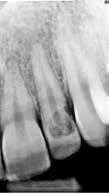

Fig. 1. A. Udsnit af panoramaoptagelse viser Ca(OH)2 uden for foramen apicale i en overkæbemolar og i sinus maxillaris (pil). B. Periapikal optagelse viser Ca(OH)2 uden for foramen apicale (pil) i en central incisiv. Tilfældet krævede kirurgisk indgreb.

Fig. 1 A. An orthopantomography section showing Ca(OH)2 beyond the apical foramen of maxillary first into the maxillary sinus (arrow) and (B) a periapical radiograph with Ca(OH)2 extrusion beyond the apical foramen (arrow) of a central incisor which required surgical intervention.

Ved mistanke om malpraksis vurderer man behandlerens handlinger i alle stadier i relation til opgavens kompleksitet og tager stilling til, om disse lever op til normen for almindelig anerkendt faglig standard. De mest omfattende skadevirkninger ses i forbindelse med anvendelse af endodontiske skyllevæsker og andre medikamenter, fx ulykker med natriumhypoklorit eller skader på nervevæv eller i sinus som følge af udpresning af calciumhydroxid igennem foramen apicale (Fig. 1A og B) (5,6). Sådanne uheld vurderes ofte til at være undgåelige, idet tandlægen ikke har levet op til normal faglig standard. Frygt for at begå procedurefejl eller andre utilsigtede hændelser bør dog ikke få klinikeren til helt at afstå fra at foretage endodontiske behandlinger (7).